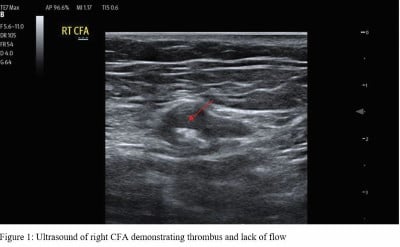

Given the patient’s sudden onset of back pain, past medical history significant for extensive cardiovascular comorbidities, cool extremities, and absent pedal pulses on physical exam, there was considerable concern for significant vascular compromise including aortic dissection, abdominal aortic aneurysm, and lower extremity ischemia. Point-of-care ultrasound study of the abdominal aorta showed absent flow in bilateral common femoral arteries, but no dissection flap or aneurysm (Figure 1).